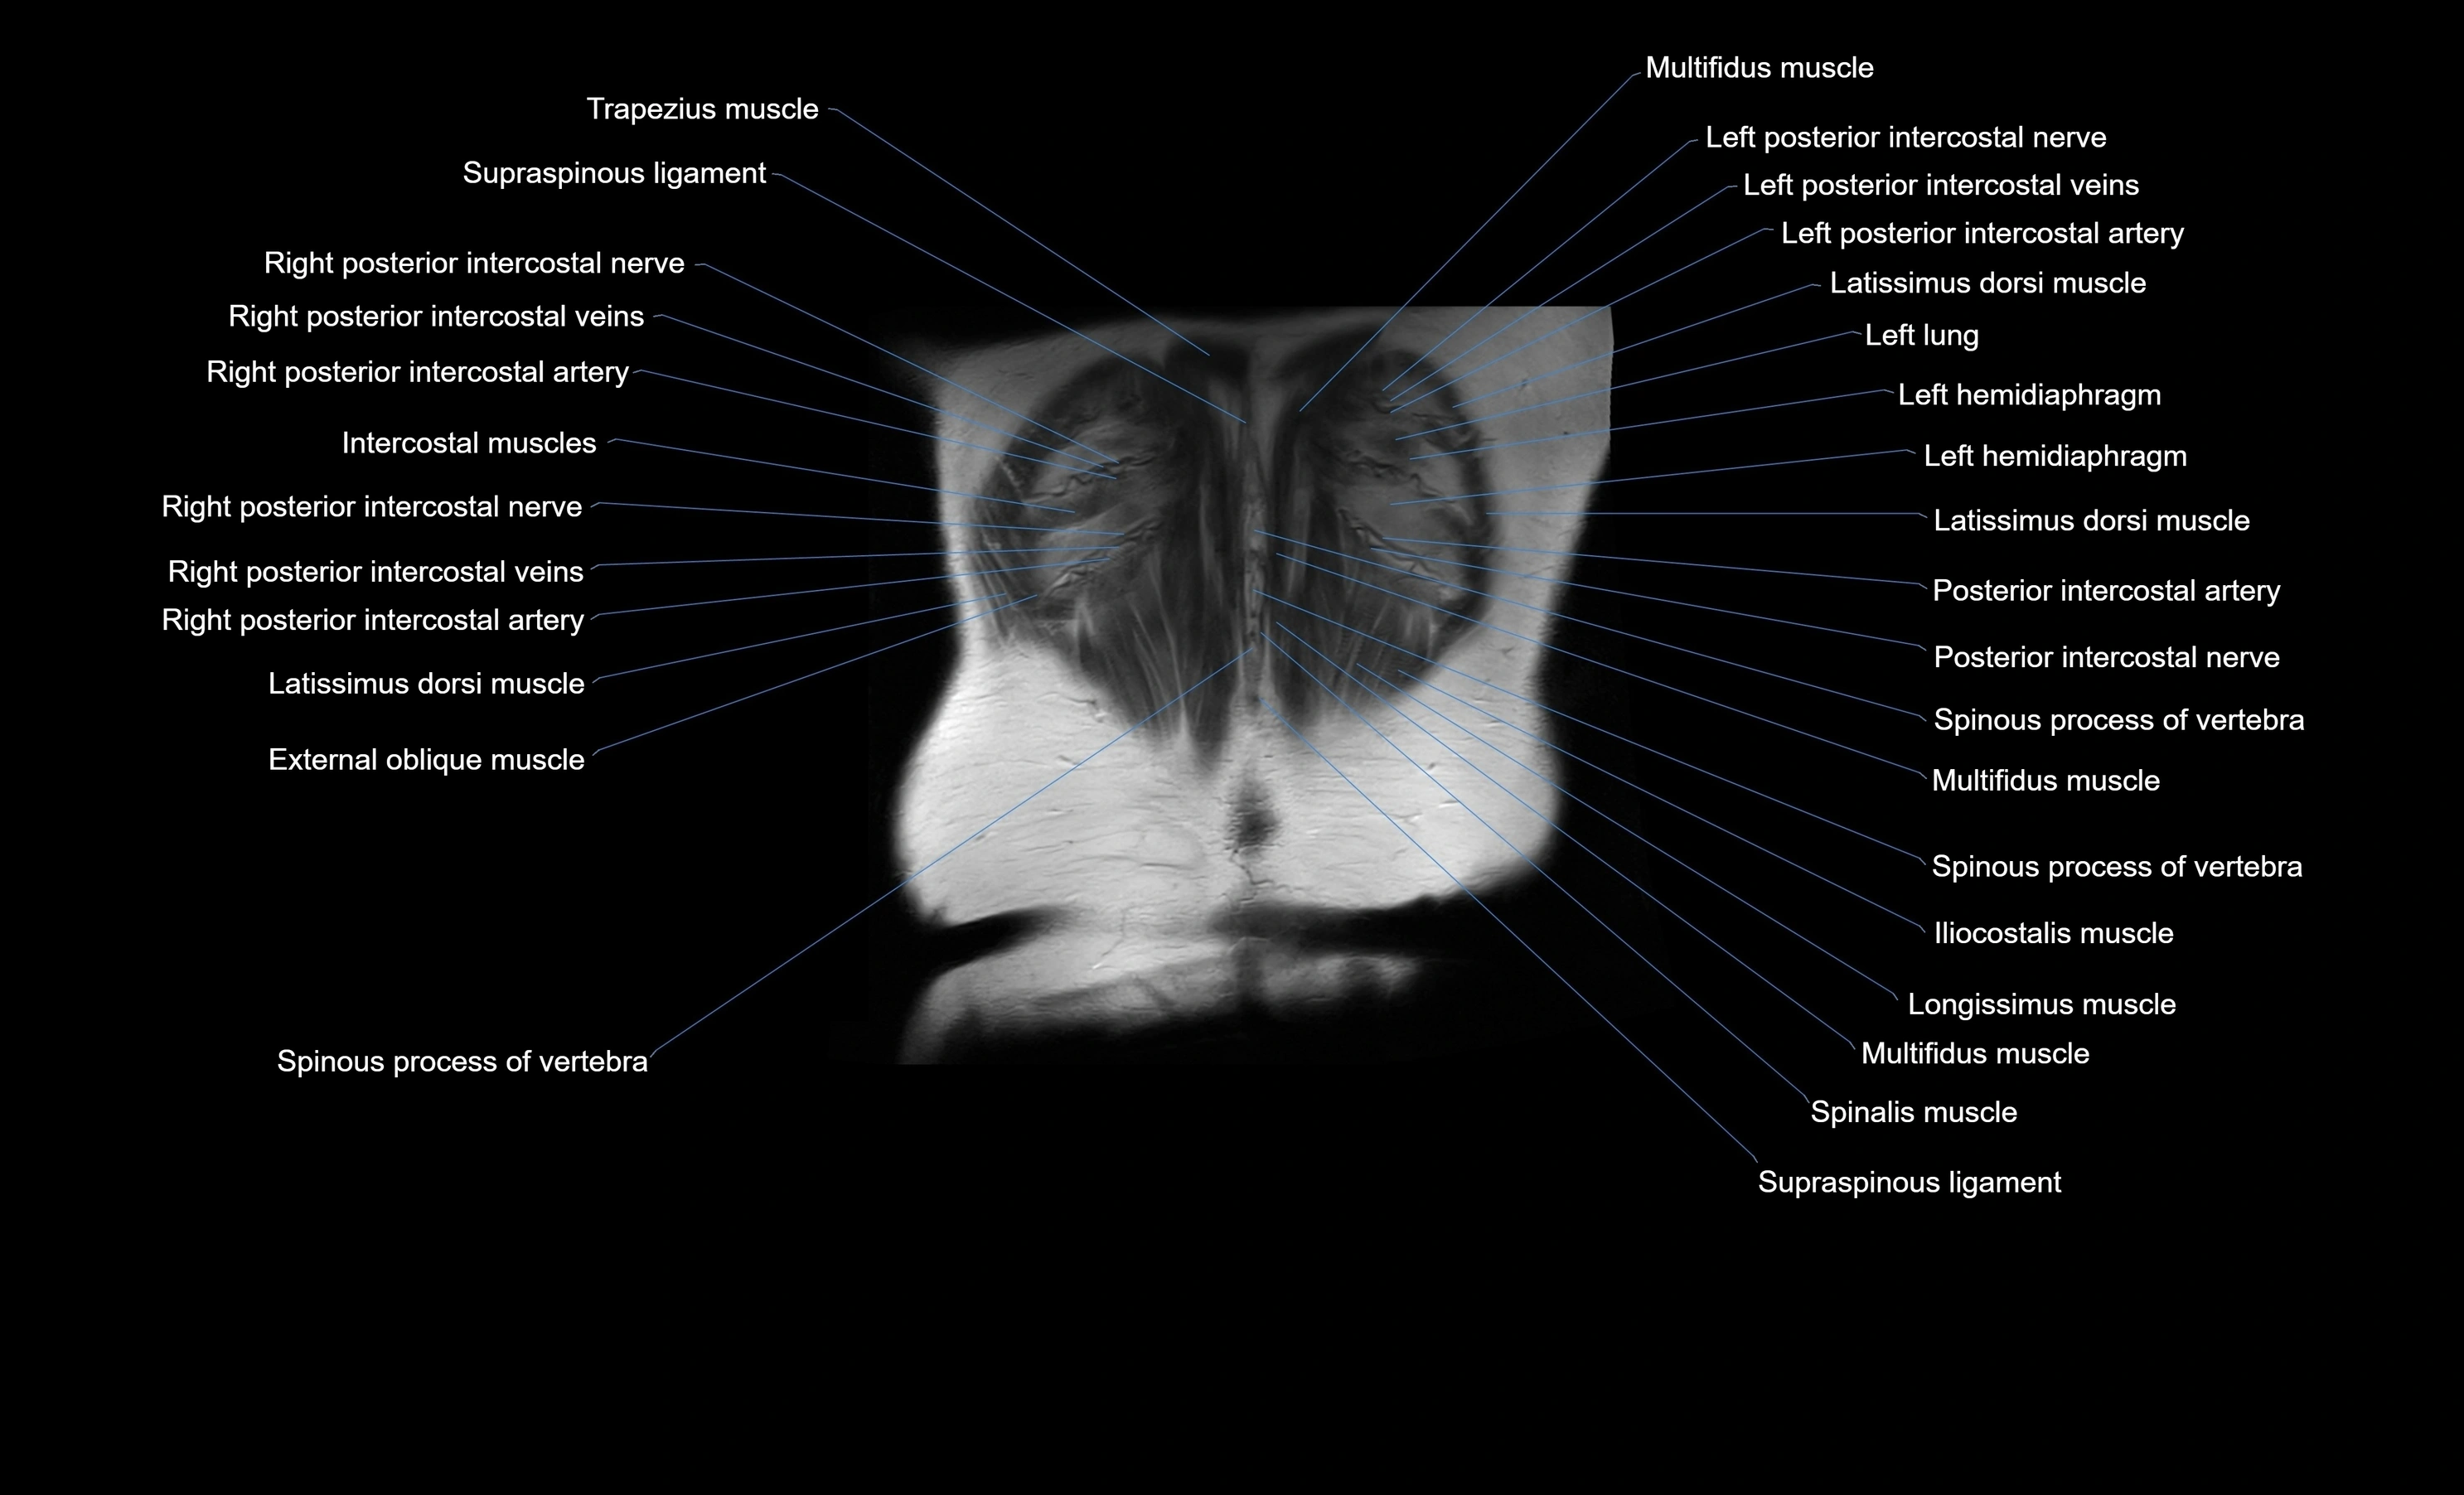

MRI images